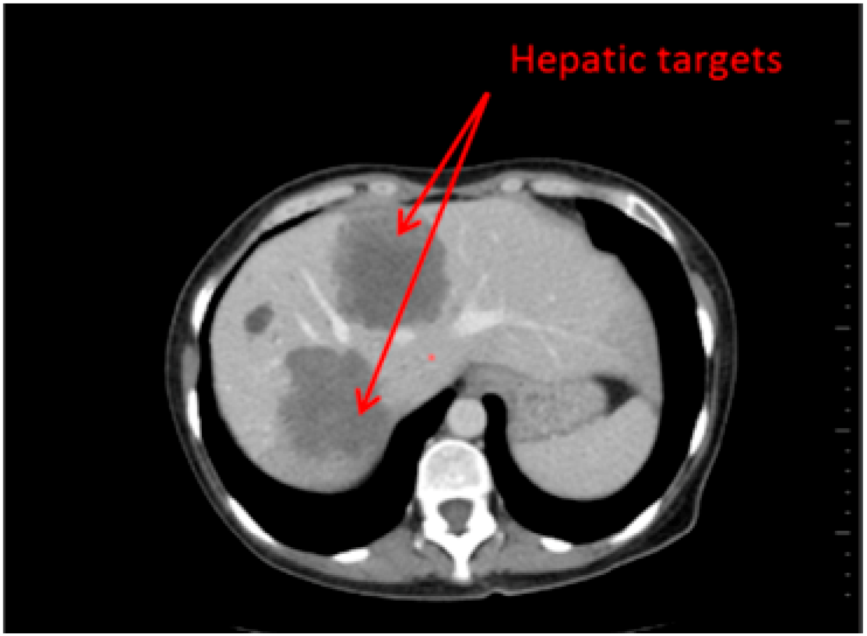

- Reading with dedicated software: Determination of RECIST response with the dedicated application for oncologic follow ups, Myrian® XL-Onco, with specific functionalities:

- 3D target matching technology to facilitate lesion localisation in the follow up study.